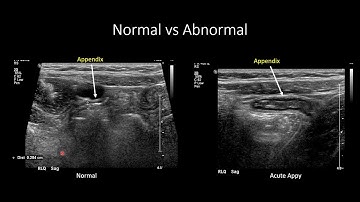

Appendix Ultrasound Normal Vs Abnormal Image Appearances | Appendicitis USG Scan